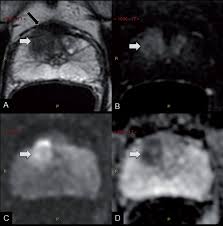

Revisiting Quantitative Multi Parametric Mri Of Benign Prostatic Hyperplasia And Its Differentiation From Transition Zone Cancer Springerlink

Revisiting Quantitative Multi Parametric Mri Of Benign Prostatic Hyperplasia And Its Differentiation From Transition Zone Cancer Springerlink from media.springernature.com